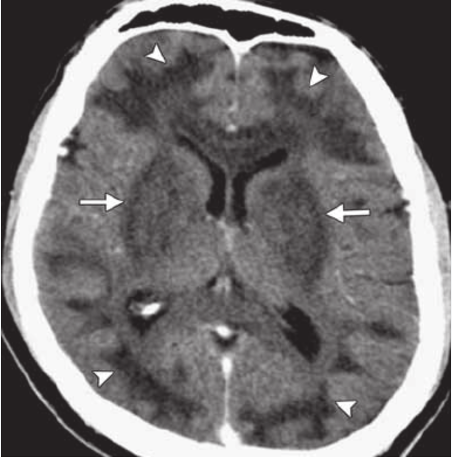

Basal Ganglia Abnormalities on Imaging: CT findings that can be seen with methanol toxicity in some cases include apparent ischemic or hemorrhagic abnormalities in the basal ganglia, such as the putamen in the case pictured below. These are typically bilateral. These are non-specific and are also seen in causes of prolonged hypoxia, prolonged hypotension, and carbon monoxide poisoning.

Source: Credit: https://www.researchgate.net/figure/Methanol-poisoning-in-a-41-year-old-man-who-presented-with-altered-mental-status-and_fig3_49777145